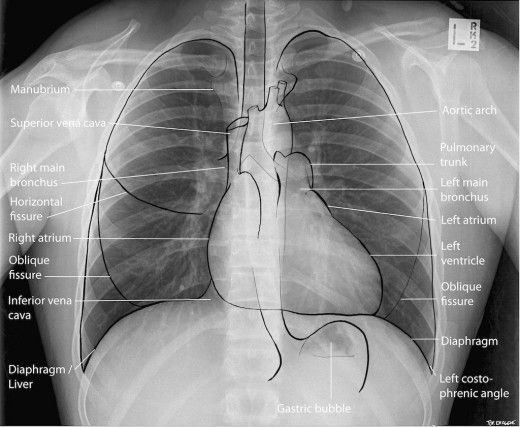

⚕Флюорография – это медицинская процедура, позволяющая получить и исследовать рентгенологическое изображение лёгких с целью выявить многие опасные заболевания. Например, злокачественную опухоль или туберкулёз на ранней стадии, когда симптомы заболевания не проявляются и диагностика болезни затруднительна.

ЧТО ПОКАЖЕТ ФЛЮОРОГРАФИЯ:

· поражения тканей органов;

· участки воспалений;

· склероз, фиброз;

· последствия травм;

· инородные предметы.